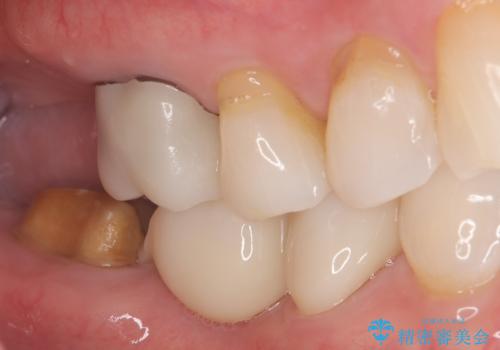

- 主訴:右下のセラミックのブリッジが何度も同じところで折れて壊れてしまう。

対合歯との咬合関係において、右下7番目と6番目の被せものの連結部がたわみやすい環境にあったため、ブリッジの新製ではなくインプラント治療を行いすべての歯を単冠仕上げとすることにしました。

何度も右下6、7間でブリッジが折れてしまうとのことでした。対合歯とブリッジの連結部が強く当たりたわみやすい状態でした。破折しずらい金属を使用したブリッジの選択もありましたが、支台歯(右下7)が失活歯場合、破折リスクが高く、破折してしまった場合にまたブリッジを外しての再治療になってしまう可能性を説明したところ、全て単冠仕上げとできるインプラント治療を希望されました。